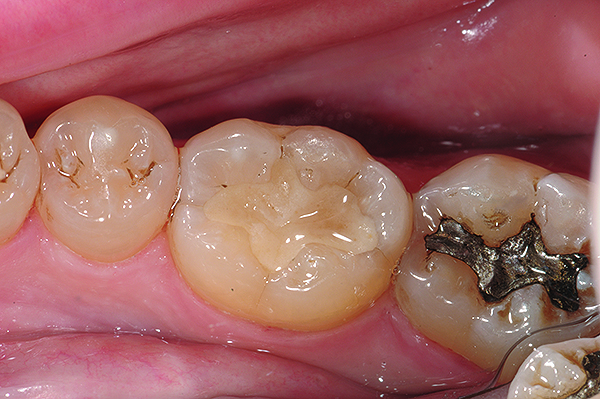

Fig 11. Completed bulk-filled GIC restorations showing excellent esthetics and surface smoothness.

Figure 11